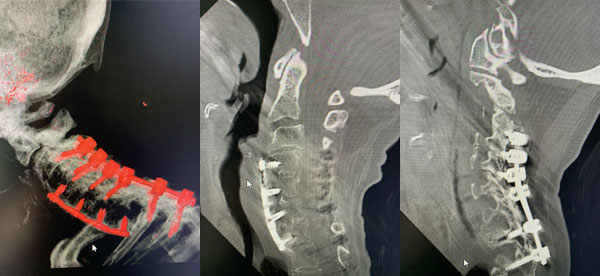

Figures 2a, b, c: Preoperative sagittal CT scans of the cervical spine demonstrating preoperative instrumentation. Note degenerative changes and anteriolisthesis of C2 and C3.

Figure 3: Postoperative lateral c-spine x-ray showing removal of prior long posterior construct with final short segment fusion C2-C4. Note addition of bilateral C2 pars screws.